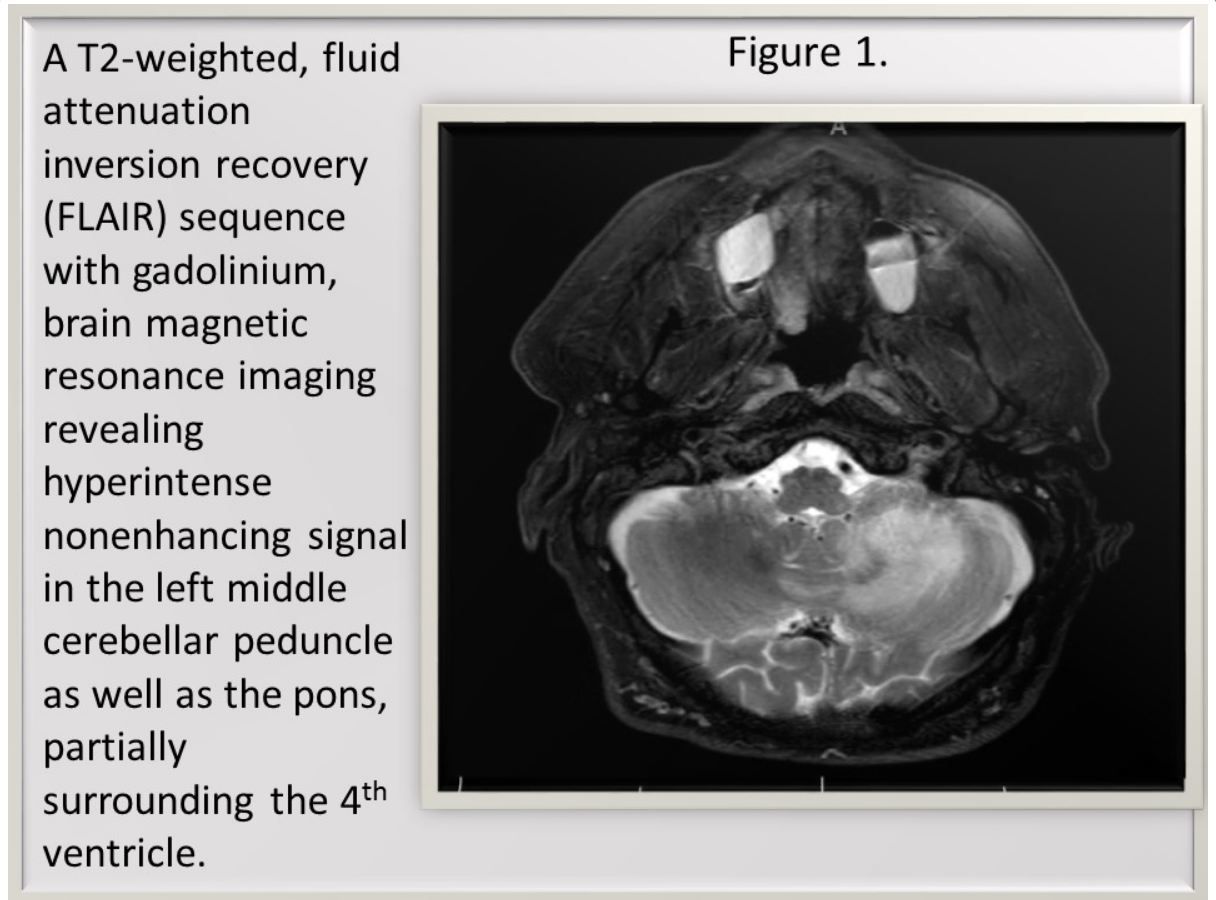

MRI scans showed a nonenhancing lesion restricted to the posterior fossa (Figures 1 and 2).

Definitive PML diagnosis requires neuropathological demonstration of demyelination, bizarre astrocytes, and enlarged oligodendroglial nuclei in the presence of JC virus.3 MRI typically shows hyperintense T2 weighted and fluid-attenuated inversion recovery (FLAIR) images, as in this patient. Gadolinium enhancement only occurs in up to 15% of cases of HIV-associated PML.3 Isolated posterior fossa PML has been reported.3